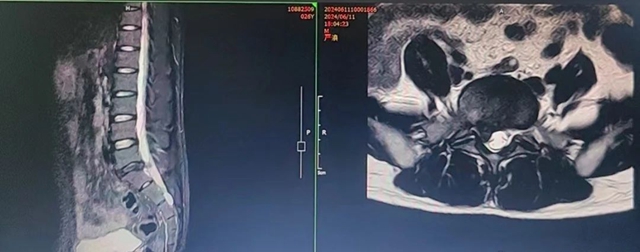

70岁的刘女士腰痛有近20年,反复发作,每次发作时,卧床休息、服药、理疗后稍有改善,劳累或外伤后又再次发作,病程迁延,还有骨质疏松性椎体压缩骨折的病史。西南医科大学附属中医医院骨伤科脊柱·肿瘤二组医生接诊后,确诊刘女士患腰椎滑脱、腰椎失稳、椎管狭窄和骨质疏松。

为了解除神经压迫、重建稳定性和正常脊柱生理序列,骨伤科脊柱·肿瘤二组专家团队决定为其实施骨水泥强化椎弓根螺钉固定+超声骨刀辅助下椎管减压扩大成型+椎间植骨融合术,术后给予中西医综合治疗,刘女士的腰痛已明显改善。